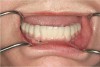

Diminished Crown Height Space

Diminished crown height space has several different solutions which depend on the patient’s anatomical limitations as well as his or her perceived needs. If the problem is the opposing arch, the solution may be fixed prosthodontics to level the occlusal plane (Figure 10A through Figure 10D). It may be intrusion of teeth with orthodontics or some combination of the two. If there is too little crown height space and the patient is edentulous, the solution may be to increase the vertical dimension of occlusion (VDO) with a removable prosthesis.17 If the patient has a partial dentition, it may involve traditional fixed prosthodontics to alter the VDO.18 The patient may need a surgical approach, such as an osteoplasty, before implant placement (Figure 11A and Figure 11B). However, without an initial diagnosis, there is no way of formulating a solution to an unknown problem.